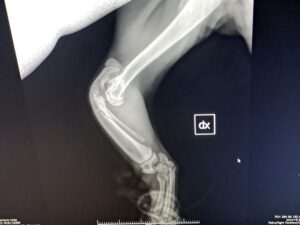

Denn inzwischen wurde Pino auf Sardinien untersucht und geröntgt. Es war sehr stark zu erwarten, dass es sich um eine angeborene Anomalie handelt. Und dies ist auch so. Pinos „Ellenknochen“ (Radius) fehlen auf der einen Seite ganz, auf der anderen Seite ist er unterentwickelt. Das führt dazu das seine Füßchen mit den Ellenbogen nicht stabil verwachsen sind und die Gelenke nicht festsitzen. Dadurch wachsen auch die Knochen nicht entsprechend und haben krankhafte Veränderungen.

Der kleine Mann ist eine „Känguru-Katze“, seine verkürzten Vorderbeine wird er nie richtig belasten können, so wie es im Moment aussieht. Ein normales Katzenleben in Freiheit ist für ihn unmöglich. Gott sei Dank zeigen sich aber keine andere Anomalien in seiner Anatomie.